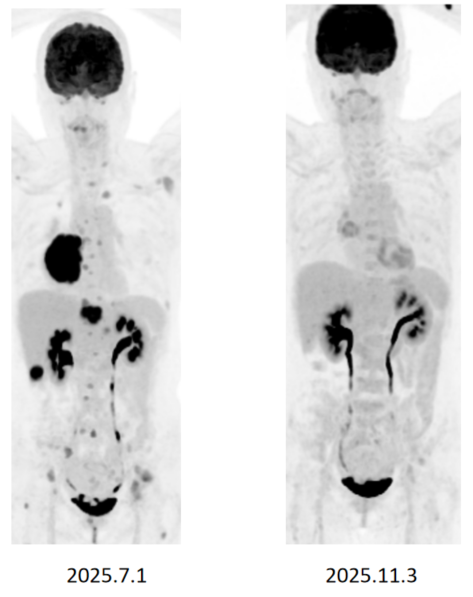

影像学检查(2025年7月1日):CT及PET-CT显示右下叶巨大肺肿块,伴多发骨、肝转移。MRI显示多发脑病灶。

疗效评估: 仅治疗1个月后,右下叶巨大原发灶及肝脏转移灶体积缩小超过80%,达到深度缓解。2025年11月1日及11月3日的影像学复查证实,患者持续维持深度缓解状态。

颅内病灶在MRI上几乎完全消失或仅残留针尖样微小病灶。

病例二具有典型的“难治”特征:EGFR突变合并MET过表达、脑转移、肝转移及ctDNA阳性。MARIPOSA研究的亚组分析已提示,包括脑转移、肝转移及TP53共突变等患者在内的预设亚组埃万妥单抗联合兰泽替尼均显示出一致的获益趋势[6]。该病例在治疗首月即实现颅内外的全面深度缓解,肺部病灶及肝脏转移灶体积缩小超过80%,颅内病灶几乎完全消失,这也成功印证了这一联合治疗方案在EGFR突变NSCLC高危亚组中的卓越疗效。